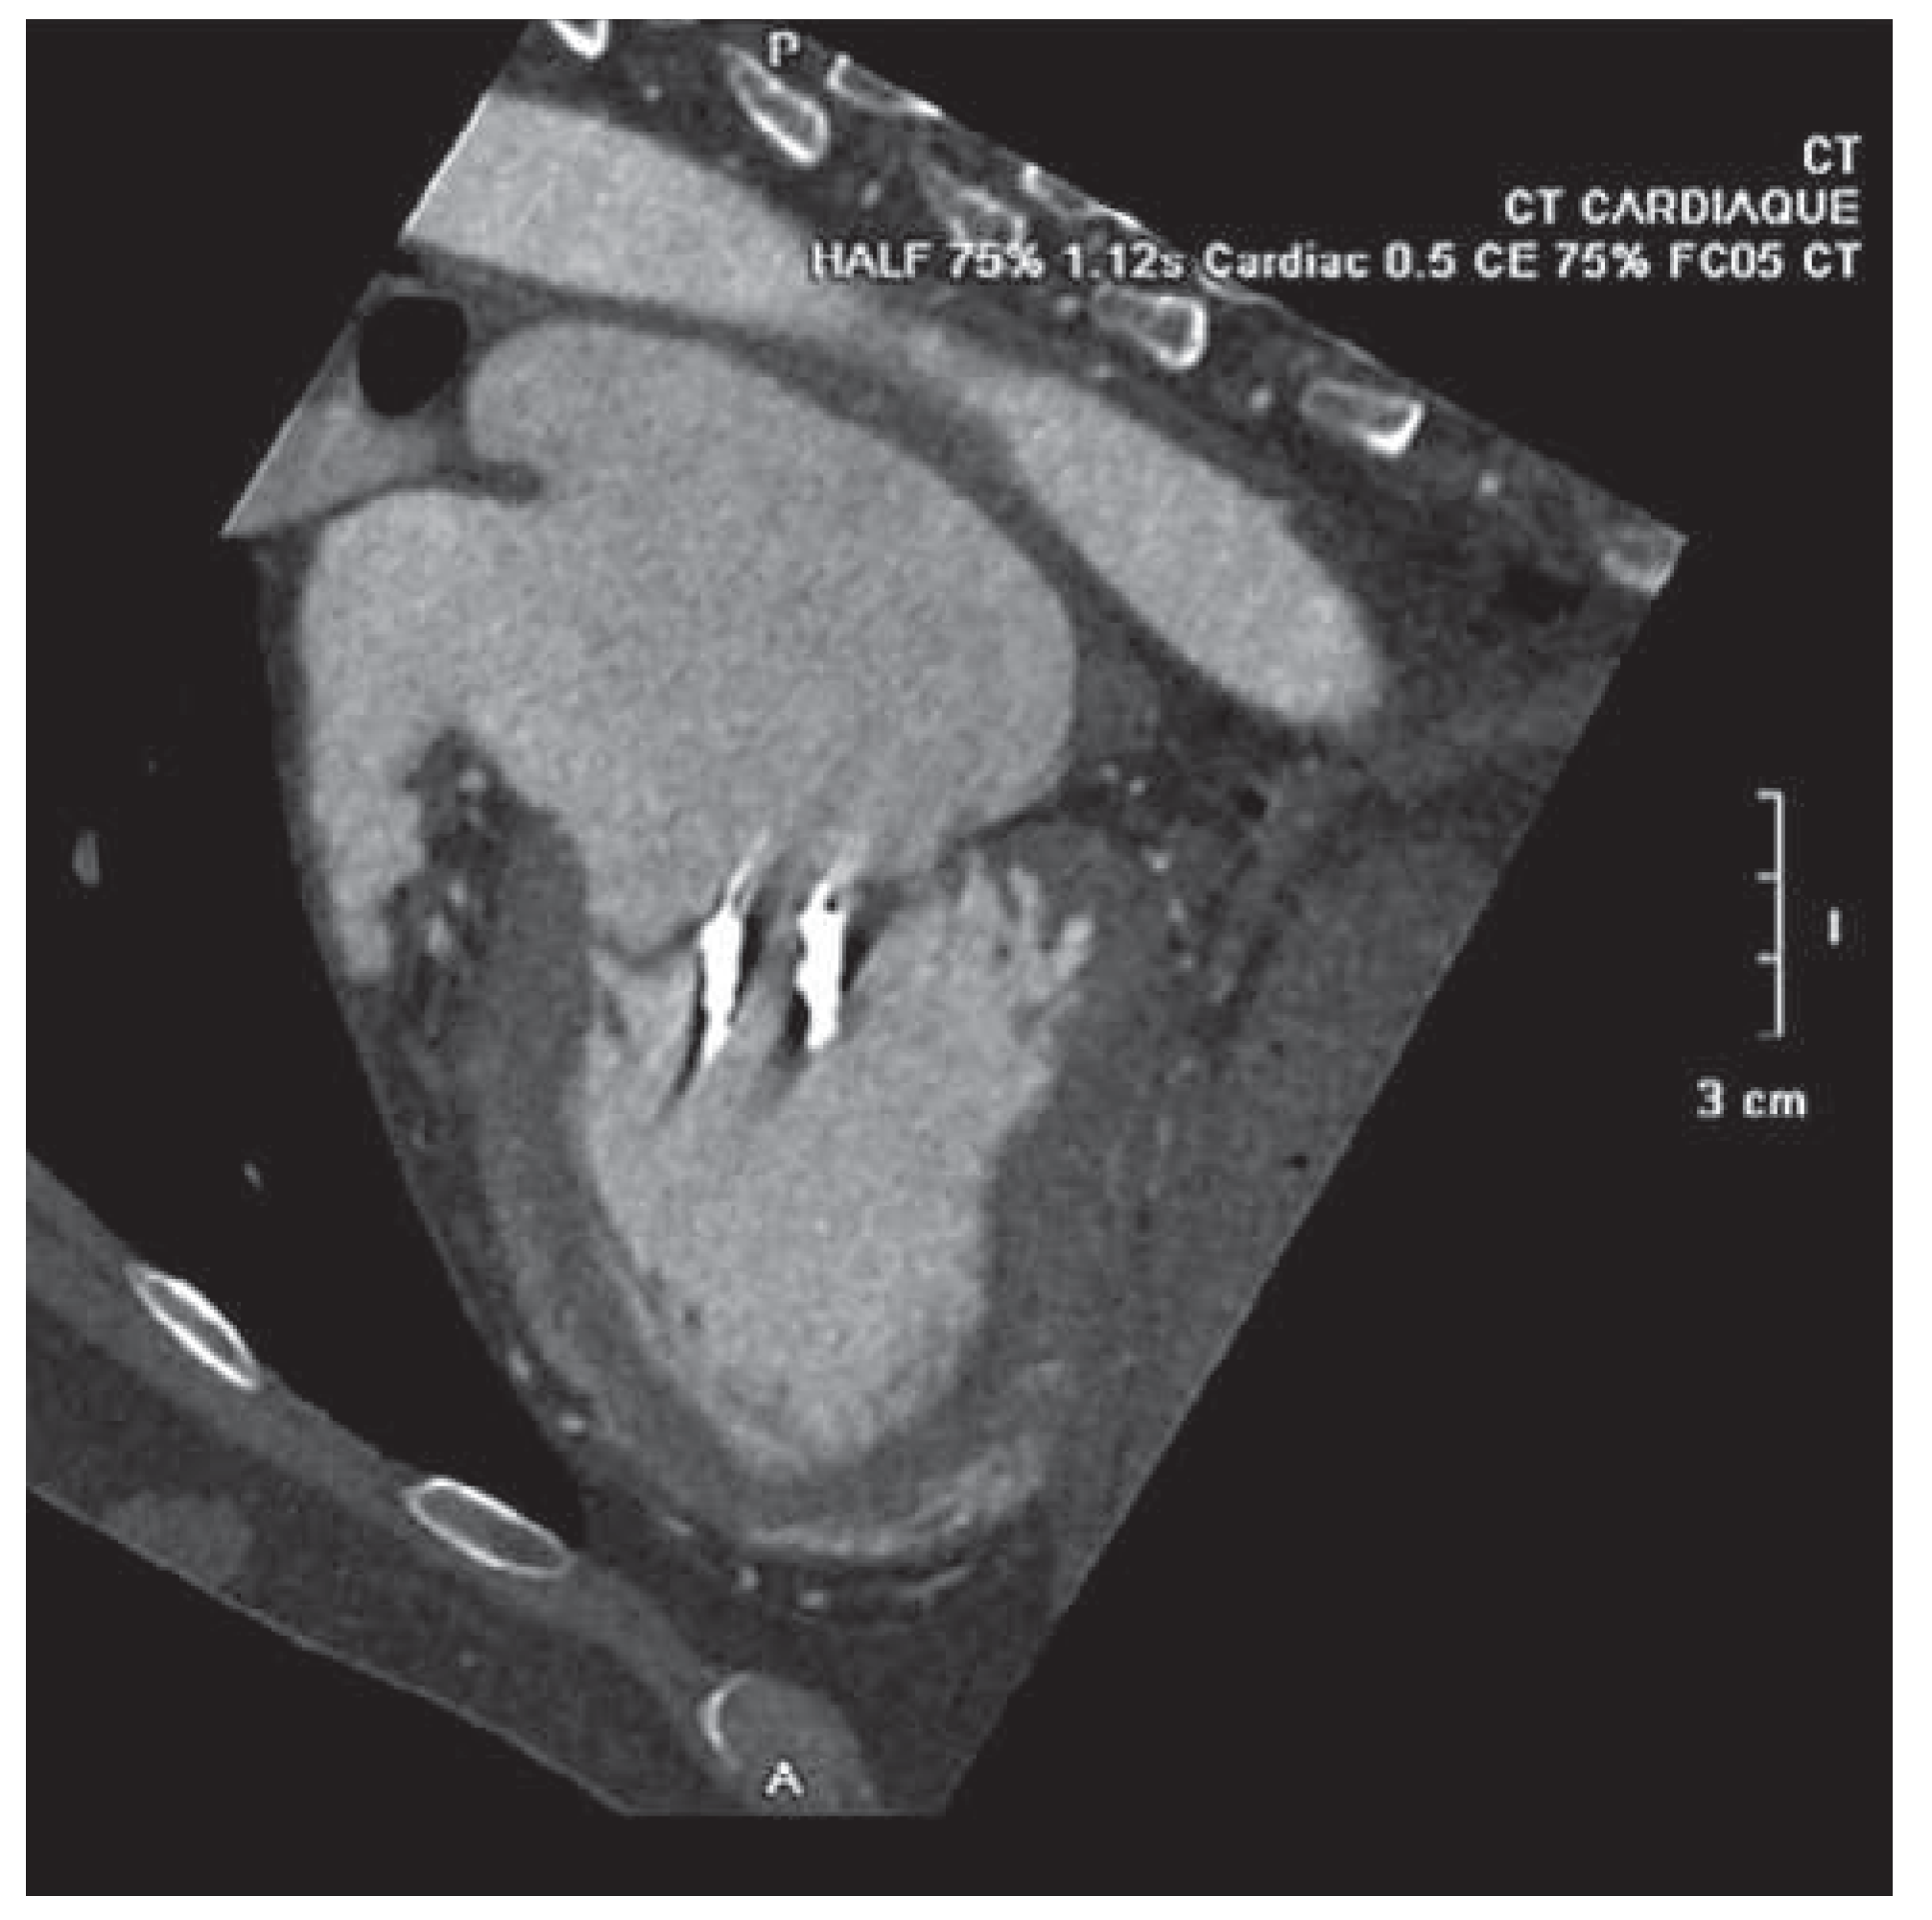

A 59-year-old man was referred to our institution for dyspnea. He had a history of mitral valve regurgitation with posterior leaflet valve prolapse. In 2006 he underwent mitral repair without annuloplasty ring implantation. In April 2012 dyspnea, NYHA II–III, recurred. Echocardiography showed grade III to IV mitral regurgitation. He was referred to another hospital, where percutaneous treatment with MitraClip™ implantation was proposed to the patient. Two MitraClips™ were implanted. Shortly after the intervention the patient complained about shortness of breath. He was seen at our hospital. Transthoracic echocardiography (Figure 1) and cardiac computed tomography (Figure 2) confirmed the clinical impression of both mitral stenosis and regurgitation with significant gradient and a valve surface of 1.7 cm2. M-mode echocardiography showed typical patterns of mitral stenosis (Figure 3). Mitral valve repair with annuloplasty could be performed with neocordals, reinforcement of the posterior leaflet and ring implantation (Figure 4 and Figure 5). Six months later, the mitral valve is fully functional and the patient is asymptomatic. This case is remarkable for a few points: firstly, mitral annuloplasty with ring implantation should be performed instead of simple repair. Secondly, equivalence of surgery with MitraClip™ implantation has been proven in some trials. However patients included in these studies were older and sicker than our patient. There are more arguments to suggest that MitraClip™ should be reserved for nonoperable patients or to patients refusing surgery. In our patient, revision surgery was probably a better option than a percutaneous approach. Valve dysfunction requiring a second intervention is almost 10 times more frequent after MitraClip™ implantation than after conventional surgery. Thirdly, even though trials about MitraClip™ are still ongoing, indications should not be lifted to younger patients, until we have clear evidence regarding the comparison of the 2 techniques. Finally, mitral valve repair with annuloplasty and ring implantation is possible after MitraClip™ implantation.

Figure 2. CT scan showing the 2 MitraClips with limitation of the opening of the valve.